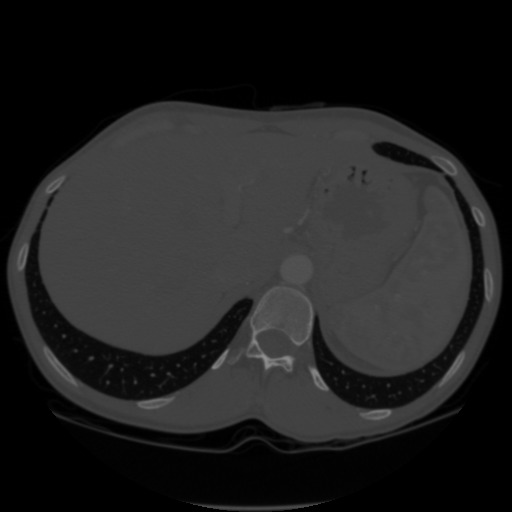

Mais un logiciel sachant que, dans un Dicom 10 bits, le dégradé allant de 0 à 255 est le premier organe, de 256 à 511 le deuxième, de 512 à 767 le troisième et enfin de 768 à 1023 le quatrième permet alors de séparer les organes pour les rendre visibles dans l'application utilisée par le praticien. Ainsi l'image suivante, retirée d'un ensemble de DICOM apparait tout gris :

Mais si on y fait appel via un logiciel dédié, nous pouvons aussi bien mettre chaque organe en couleur :